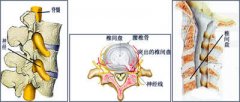

腰腿伤是指以腰部和腿部疼痛为主要症状的伤科病症,包括慢性腰肌劳损、腰椎间盘突出症、梨状肌综合症…「 阅读全文 」

临床上引起腰腿痛的原因很多,由于多方面的因素容易造成诊断不清甚至误诊,也影响了治疗效果。为避免…「 阅读全文 」